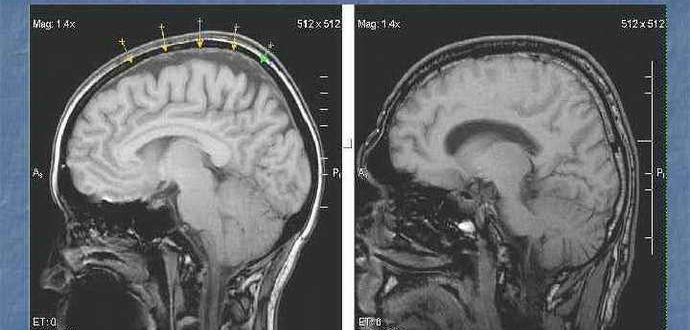

Умеренно-выраженная наружная гидроцефалия у взрослого: что это такое, признаки Гидроцефалия – обильное скопление жидкости в головном мозге. При данном заболевании наблюдается интенсивная выработка спинномозгового секрета между смежными желудочками…

Расшифровка МРТ головного мозга: результаты и заключение, норма у здорового человека Магнитно-резонансная томография – сложная, но точная диагностика, превосходящая и рентген, и УЗИ, и другие виды обследования. Однако…